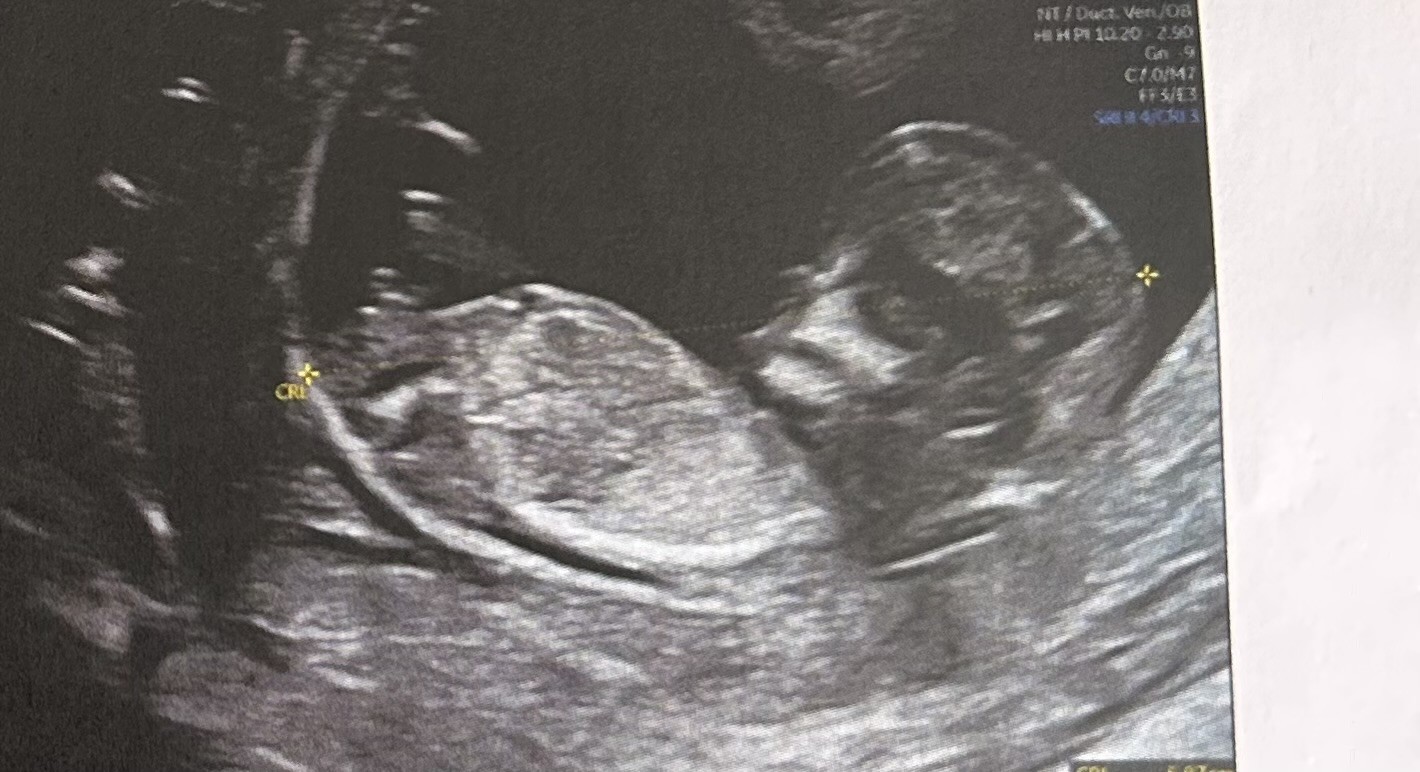

Hej i jak chłopiec czy dziewczynka ?Hej, zdjecie z pierwszych badań prenatalnych. Lekarz nie sugerował płci.

12+6

Co myślicie- chłopiec czy dziewczynka?